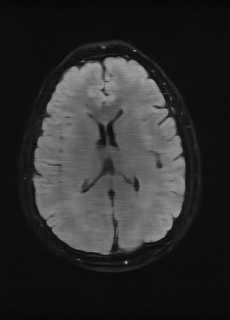

As we observe from the right image in Fig. 2, our BRM, both from MIMO and SISO settings, predicts the performance of dedicated models with a high correlation. We further choose the best three , and perform the last stage of fine-tuning accordingly to (6). A visual evaluation on real data is shown in Fig. 3. For simulated data, please refer to the Supplemental Material section.

Base on the best performing , we perceive that among , , and FLAIR, the results are best when is sampled the most. We suggest that this makes intuitive sense as images provide the best contrast out of the three sequences, which can compensate for the details lost in other images. The same observation can be made on the simulated data, where both and FLAIR show good contrast. When the time setting is changed to non-uniformity, we can see that our search for the best sampling strategy reflects the change. is sampled more as a result of faster acquisition time, while is still sufficiently sampled.

| Sequence | LR | SISO | MIMO | MIMO tuned | GT |

|---|---|---|---|---|---|

(a) 34.38/0.9371

(a) 34.38/0.9371

|

(b) 42.42/0.9883

(b) 42.42/0.9883

|

(c) 44.60/0.9920

(c) 44.60/0.9920

|

(d) 45.50/0.9940

(d) 45.50/0.9940

|

(e) PSNR/SSIM

(e) PSNR/SSIM

|

|

(f) 29.74/0.8903

(f) 29.74/0.8903

|

(g) 36.25/0.9734

(g) 36.25/0.9734

|

(h) 36.42/0.9752

(h) 36.42/0.9752

|

(i) 37.70/0.9832

(i) 37.70/0.9832

|

(j) PSNR/SSIM

(j) PSNR/SSIM

|

|

(k) 39.89/0.9311

(k) 39.89/0.9311

|

(l) 43.94/0.9864

(l) 43.94/0.9864

|

(m) 44.74/0.9883

(m) 44.74/0.9883

|

(n) 45.49/0.9894

(n) 45.49/0.9894

|

(o) PSNR/SSIM

(o) PSNR/SSIM

|